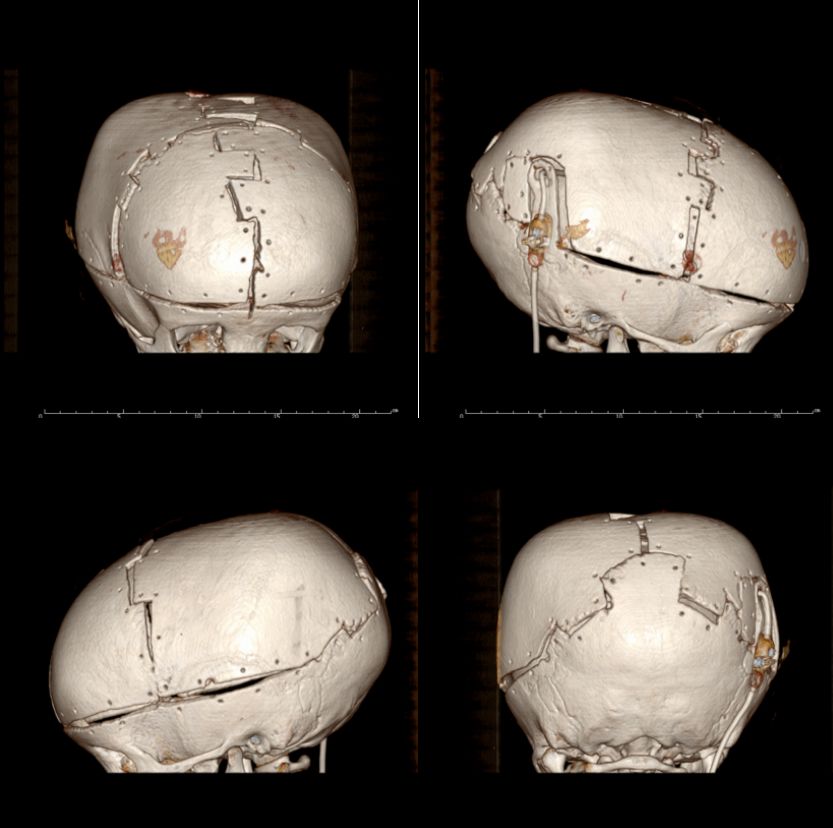

随后行患儿头颅三维重建检查(图2),并制定相应手术方案。考虑以下几点:1. 手术目的达到缩颅效果,头围能减少5cm以上,颅高减少2cm以上;2. 分流管位置保持原位,避免移位后导致分流管故障;3. 缩颅后减少的容积通过术前创造硬膜下积液以及术中抽吸脑脊液来获得空间;4. 固定上采用嵌插的方案增加固定的稳定性;5. 方案中骨瓣的设计尽量避开重要的静脉窦和骨嵴。

![]()

图2. 患儿头颅三维CT检查。